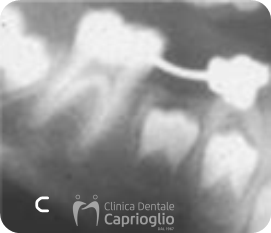

Paziente di 7 anni e 5 mesi

a) Perdita precoce di 8.5

b) Mantenitore di spazio cementato su 8.4

c) Controllo radiografico percorso di eruzione del 4.5

d) Eruzione completata del 4.5